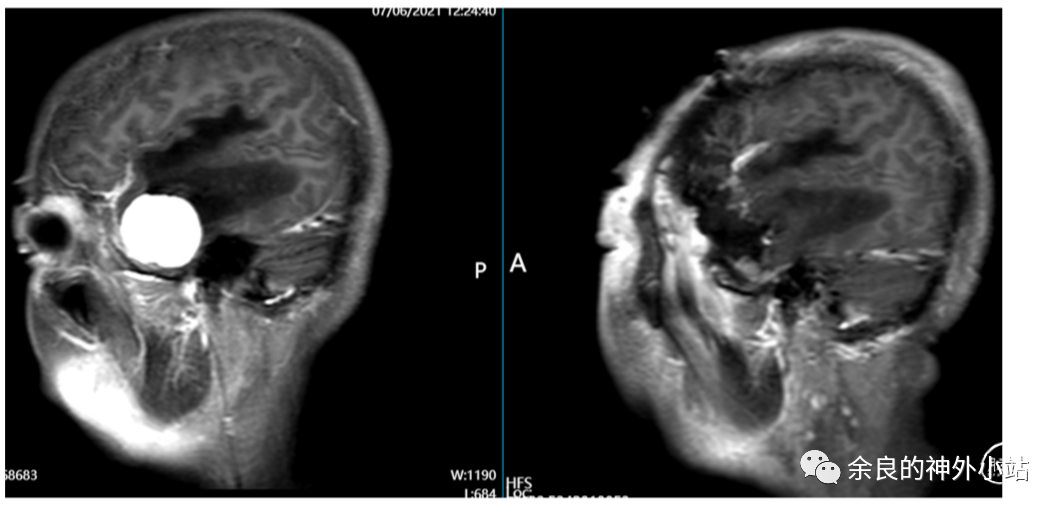

术前颅脑 MRI 增强和术后 CT 平扫(术后 MRI 在预约中).

手术日期:2021 年 6 月.